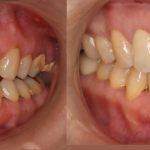

今は大きな影響がなくても段々と噛み合わせが合わなくなってきたり、隣の歯が倒れてきて隙間ができ食べカスがつまりやすくなり虫歯が出来てしまうなどのリスクもあるそうです。

一般的には、インプラントや部分入れ歯、ブリッジなどの治療方法があります。

患者様ひとりひとりのお口の状態や、それぞれの治療のメリットデメリットは様々です。